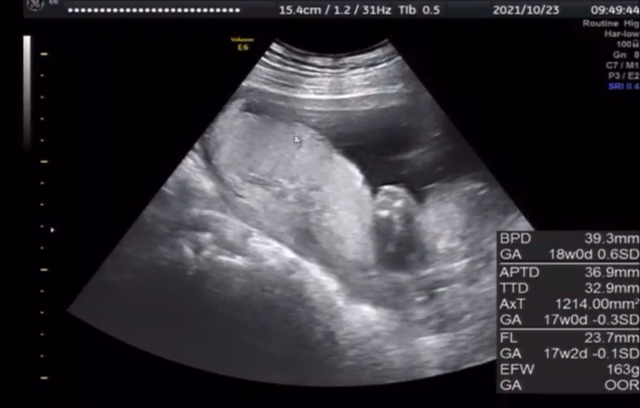

17w3d 妊婦健診☆